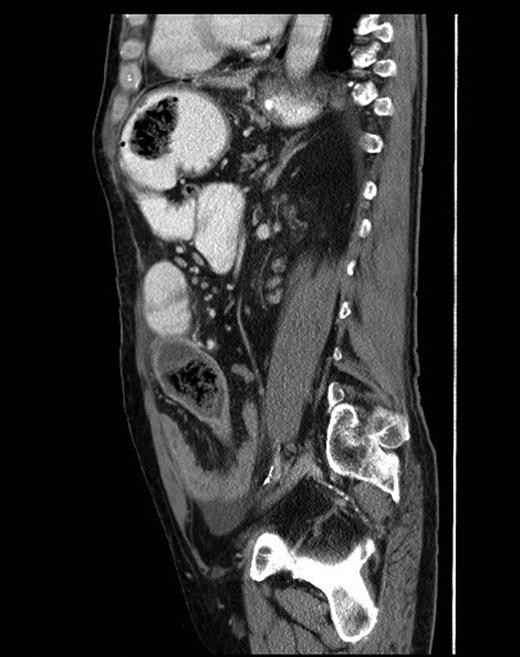

A contrast-enhanced CT scan was arranged and it showed features of SBO with collapse of the terminal ileum. There was evidence of a previous gastrojejunostomy with suspected foreign bodies in the stomach and proximal ileum. (Figs 1 and 2) .

Sagittal CT scan view showing foreign bodies in the stomach and the ileum with transition point in the small bowel.